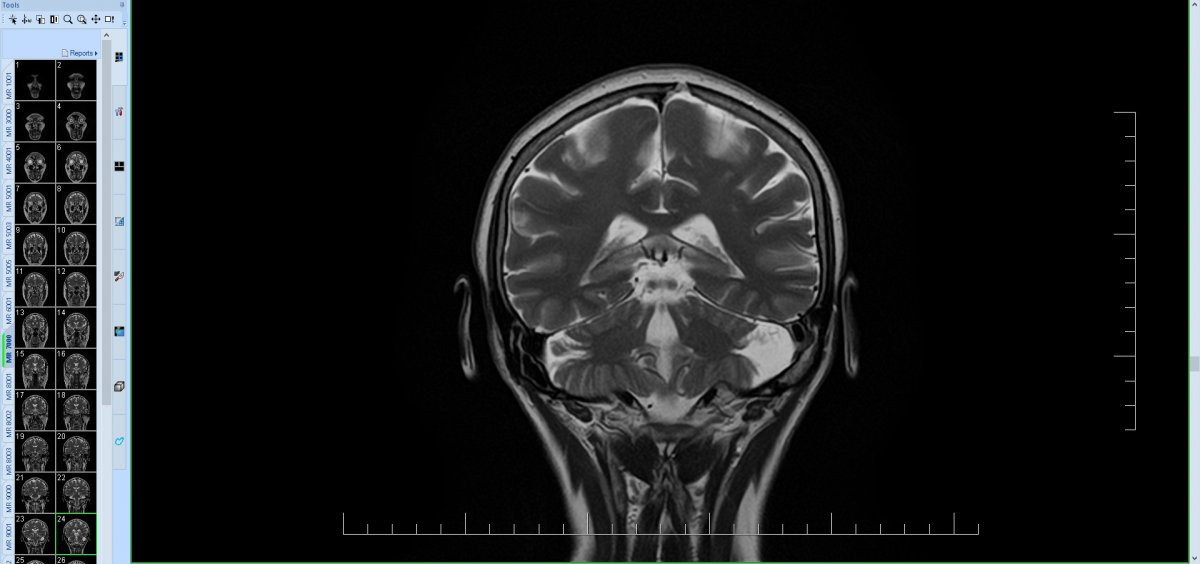

Pacientka nar. 1964 s bolestmi hlavy od r. 2020 s maximem za levým uchem, postupně vyzařování do oblasti tváře, oka, TPM skloubení až do celé levé poloviny hlavy, spíše narůstající intenzita s kolísáním a přechodnými suicidálními verbalizacemi. Od r. 2021 i závratě a zhoršení stability stoje a chůze, bez pádů. Objektivně mírná dystaxie na LHK, chůze a stoj spont. o širší bázi, v BR postojích patrná závislost na zaměření/odklonění pozornosti. Dle MR mozku arachnoidální cysta zadní jámy lební vlevo laterálně vel. 30 x 16 x 26 mm s lehkým tlakem na levou mozečkovou hemisféru, MR AG bez známek neurovaskulárního konfliktu. Konzultováno neurochirurgické pracoviště FN U Sv. Anny v Brně - operační řešení neindikováno, pacientce sděleno, že potíže s nálezem na MR nesouvisí a je třeba hledat jinou příčinu. Doplňována MR C páteře, kde artróza C1/2 a osteochondróza C5/6 s foraminostenózou bilat. více sin., MR TPM skloubení s mírně ventrálnější pozicí disků, vlevo i s mírnou nehomogenitou signálu ve ventrální porci. Pokus o obstřik n. occipitalis major pod UZ kontrolou ve FN bez pozitivního efektu, dle pac. naopak. následně zhoršení obtíží. Vzhledem k susp. psychogenní nástavbě (dlouhodobá konfliktní situace v rodině pacientky) vyšetřena i v amb. pro funkční poruchy a v amb. pro léčbu bolesti, psychoterapii odmítá, na psychiatrii již sledována s dg. somatoformní poruchou, dlouhodobě léčba venlafaxinem + gabapentinem s jen mírným snížením intenzity bolestí, Pregabalin bez efektu, léčebné konopí i léčba opiáty s nežádoucími účinky. Pacientka přesvědčená o souvislosti bolestí s cystou, opakované telefonické konzultace oš. neurologa i několikrát měsíčně pro bolesti, požaduje řešení.

obtíže nesouvisí s arachnoidální cystou, tlakové změny nevidím (škoda, že takto vysloveno), spíše lokální atrofie, nejedná se pravděpodobně o pozůstatek nějakých akutních změn, vrozená. Bez NV konfliktu.